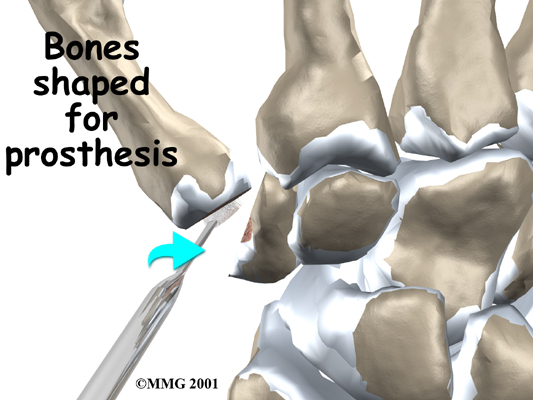

A burr (a small cutting tool) is used to make a canal into the bones that form the thumb joint. The surgeon sizes the stem of the prosthesis to ensure a snug fit into the canal and inserts it. When the new joint is in place, the surgeon wraps the joint with a strip of nearby tendon. This gives the new implant some added protection and stability.

A burr is used to make a small notch, or canal, in the ends of the two bones. The surgeon shapes the notch so the ball-shaped implant will fit snugly in the joint. The implant is placed between the ends of the shaped bones.

View animation of stem sizing and insertion